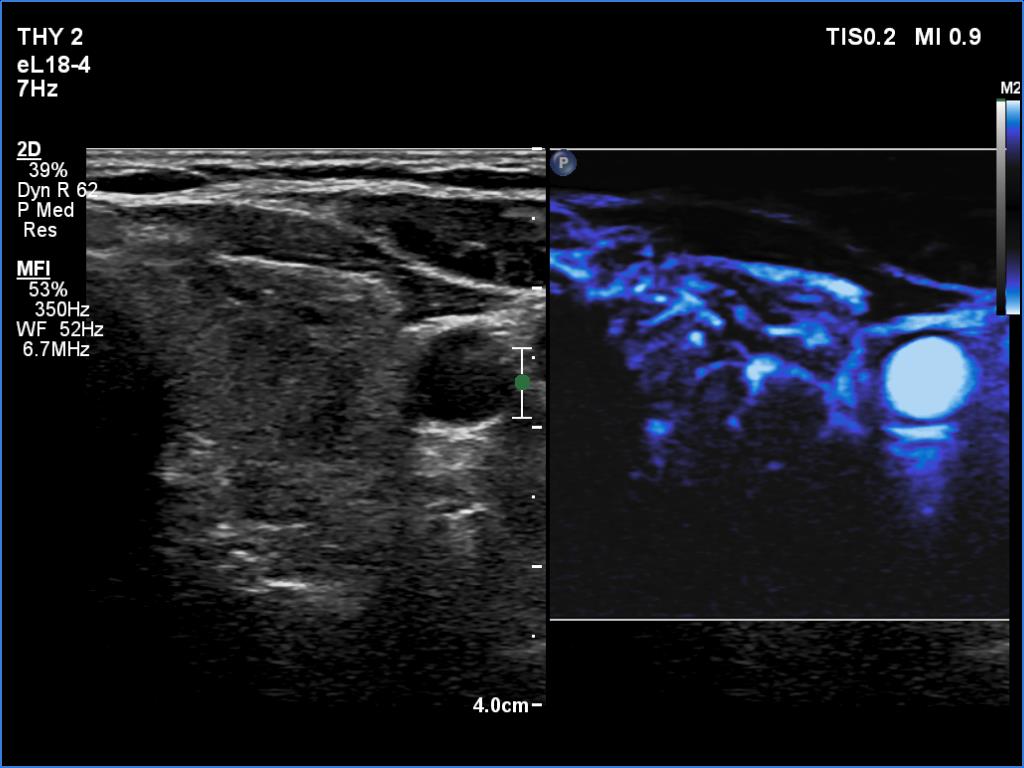

Left lobe, transverse scan, microflow imaging.